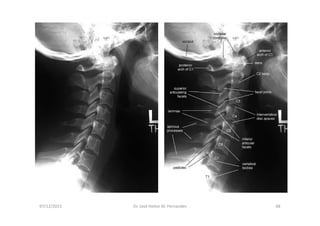

Anatomia Radiológica Cervical

1. Radiografia Simples

Radiografia da coluna cervical

Série de Radiografias Simples

da Coluna Cervical

• 1- Incidência AP com a boca aberta (para visualizar C1-C2);

• 2- Incidência AP cervical inferior;

• 3- Incidência cervical lateral (perfil);

• 4- Incidências oblíquas direita e esquerda;

• 5- Incidências adicionais:

- Incidência lateral em flexão e extensão

- Incidência de Fuch

- Incidência dos pilares de Boyleston

07/12/2015 Dr. José Heitor M. Fernandes 65

AP Lateral

07/12/2015 Dr. José Heitor M. Fernandes 66